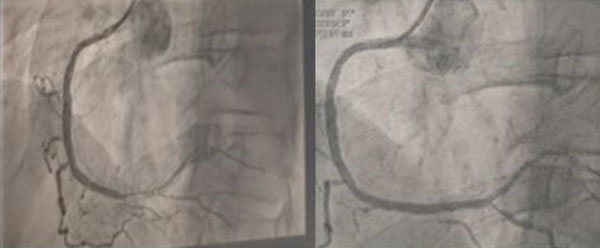

We report the case of a 31-year-old non-obese patient, with no particular personal history, presenting with a notion of a stroke in the mother at the age of 52 and an acute coronary syndrome on two occasions at the age of 44 (Figure 1 and Figure 2). He was hospitalized for a myocardial infarction in inferior left ventricular ejection fraction (LVEF) 62%, revascularized on the right coronary by primary angioplasty, at 96 minutes (Figure 3). Clinical examination was normal, including a blood pressure (BP) of 135/82 mmHg and a heart rate of 92 beats/min. The lipid profile showed hypercholesterolemia (HCT) with LDL-CT of 3.64 g/L, HDL-CT of 0.32 g/L, and TG of 2.1 g/L. The patient had a MedPed score of 12 points associated with genetic sampling, showing a copy of the LDL receptor gene.

Figure 3: On the left is a coronary angiography image showing a tight stenosis of the right coronary in its segment, while on the right is a revascularized right coronary.